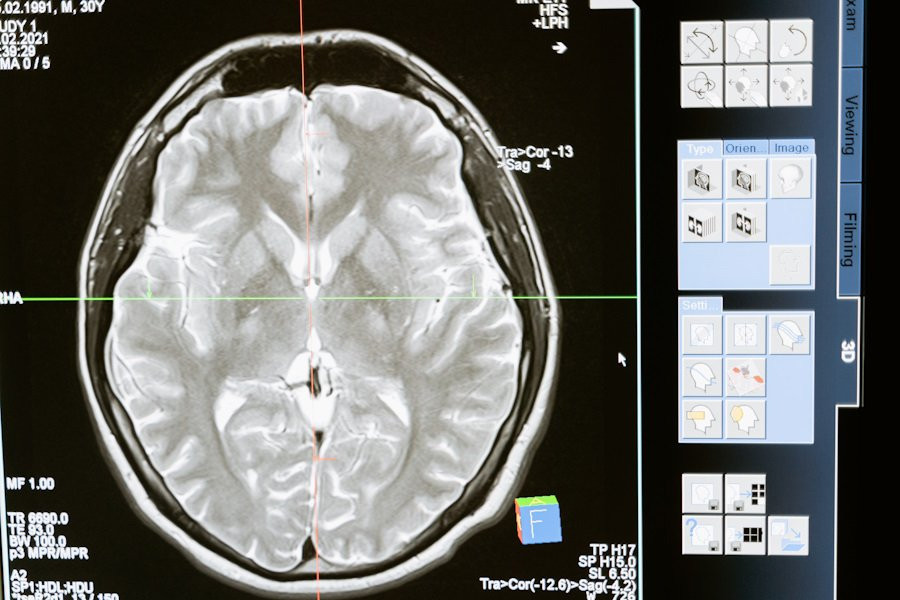

Фото из открытых источников

Воспользовавшись функциональной МРТ (фМРТ), специалисты определили конкретную область мозга, отвечающую за руминацию, — это дорсально-медиальная префронтальная кора (ДМПК).